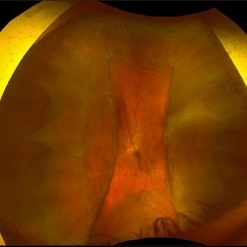

Giant Retinal Tear with Choroidal Detachment

Giant Retinal Tear with Choroidal Detachment

Jun 12 2024 by Anand Temkar

Intra operative still of a 34 year old male showing Giant Retinal Tear with Choroidal Detachment.

Photographer: Dr.Anand Temkar- Retina Foundation, Ahmedabad

Condition/keywords: choroidal detachment, giant retinal tear